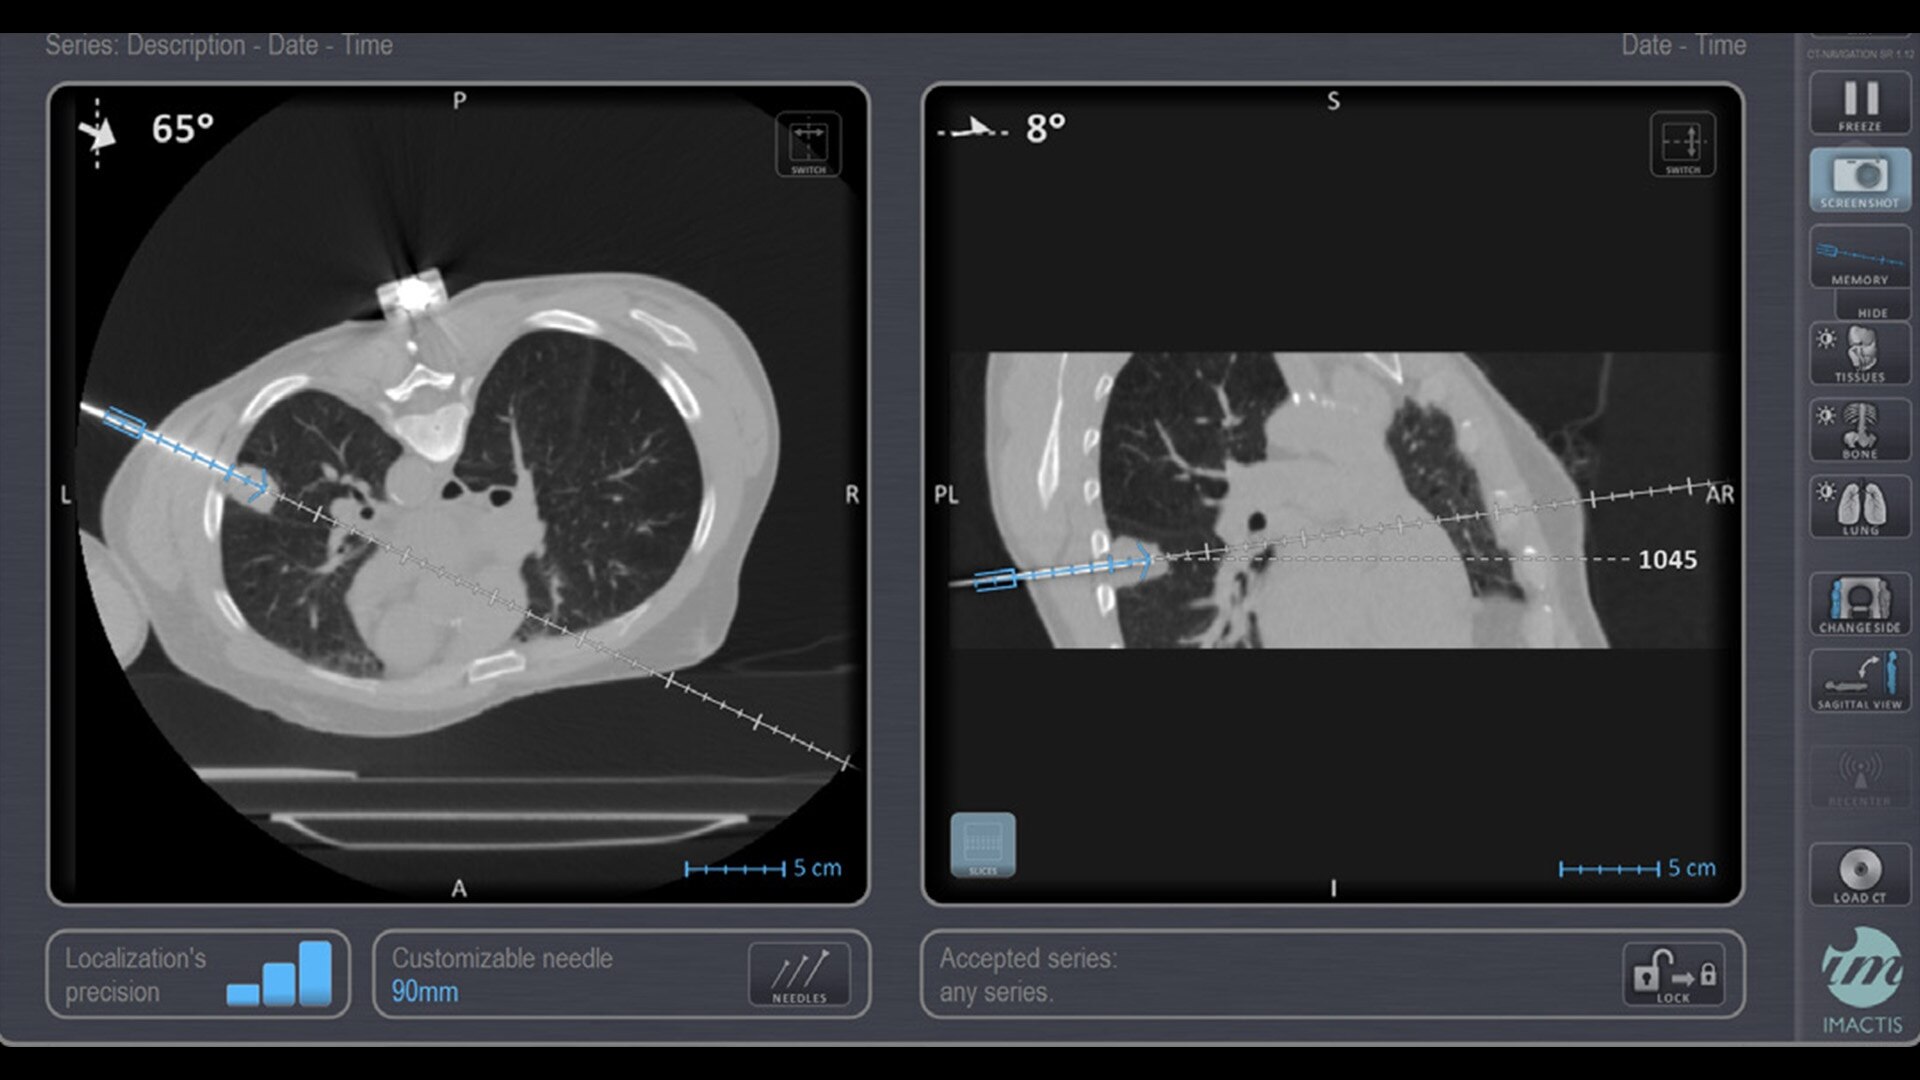

In interventional radiology, the success of the percutaneous procedure depends on correct needle positioning. The Imactis system helps the radiologist place one or more needles with great accuracy, in less time and with fewer control scans.

The CT navigation solution optimizes the efficiency and potentially helps to improve clinical outcomes of biopsies, thermoablations, drainages, infiltrations, electroporations and osteosynthesis.

With real-time image reconstruction, live interactive navigation and no limit in angulation, the optimal clinical choices are clear.

Live 3D needle tracking, precise reproduction of your planned trajectory and continuous needle depth measurement help ensure optimal needle placement.